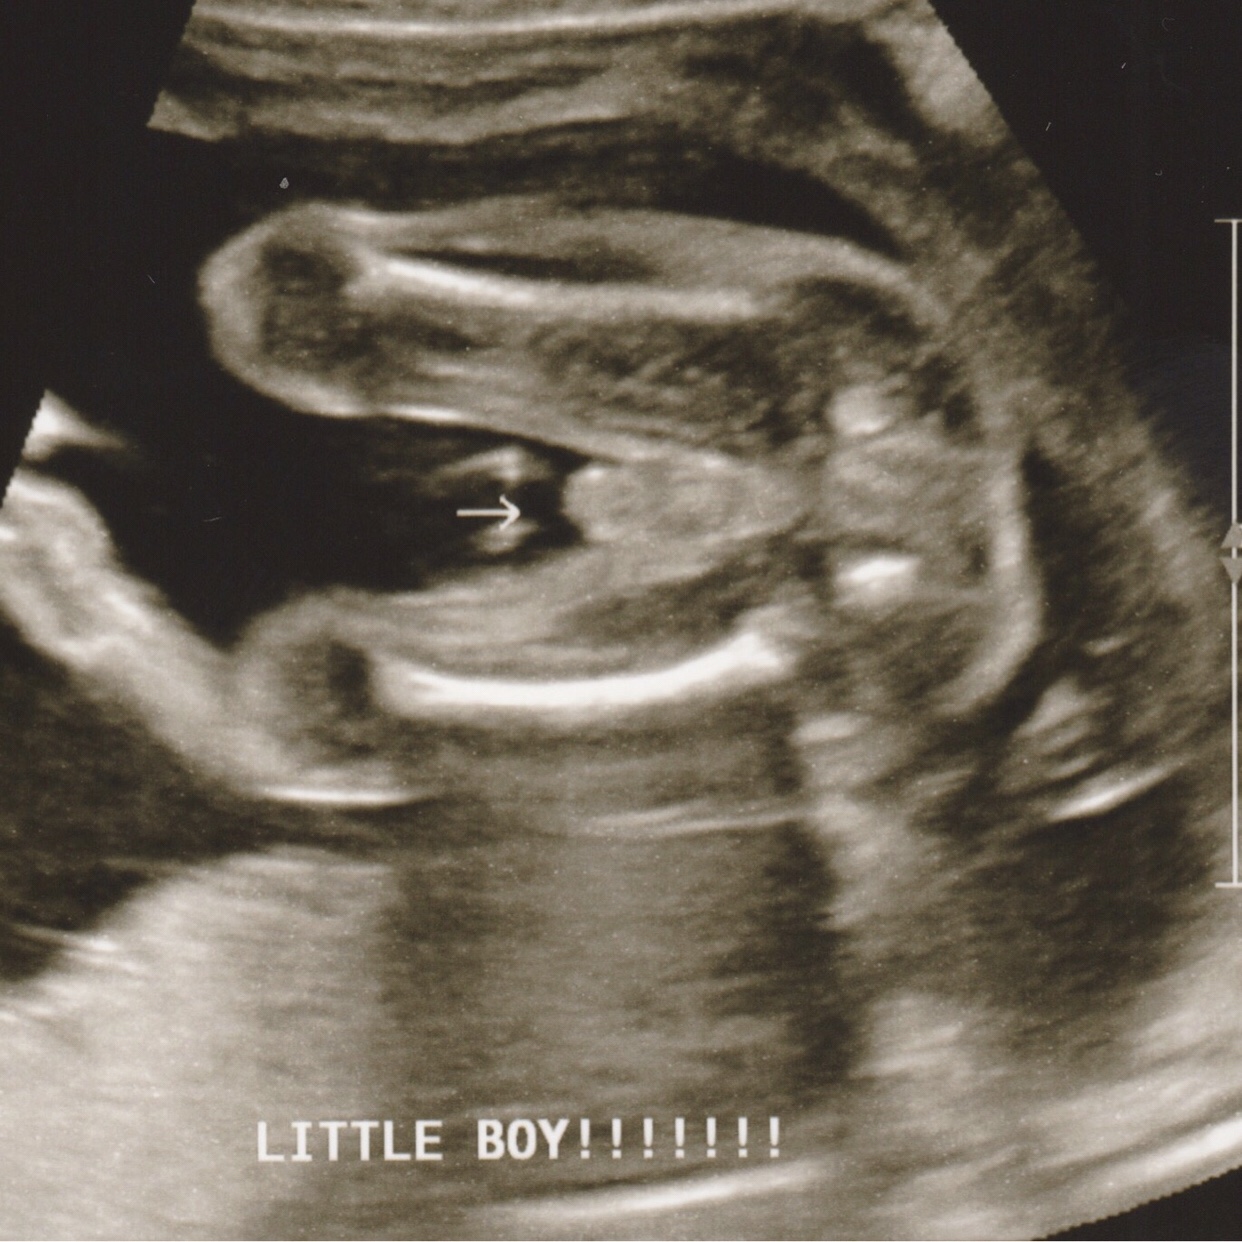

In the meantime, our anatomy scan was scheduled for my 20th week. We went on July 5th with both of my parents and Ryne’s mom and we all got to experience it together. It was magical. The ultrasound technician was informative and kind, explaining all the bits of the baby that she was examining – we saw everything from inside our baby’s brain, to the chambers of his heart, to a close-up of his face, his tiny toes, and finally the confirmation that he was, as I suspected, a boy. We rejoiced tentatively in the idea of having a son, knowing that it would be weeks before we would find out if he would ever be born.

Finally, the day of our amniocentesis arrived. We met with our genetic counselor, an amazing and empathetic woman who explained the procedure, discussed the implications of cystic fibrosis, and was understanding of our decision to terminate our pregnancy if we received bad results. We then went through another anatomy scan, getting another detailed peek at our seemingly healthy (and large) baby boy. A doctor performed the amnio procedure after fully explaining it and detailing the risks. She and a nurse prepared my stomach by thoroughly cleaning it with iodine, then, while watching the ultrasound screen like a hawk, she inserted a very long, thin needle through my skin and uterine muscle, into my uterus to extract 30 ccs (cubic centimeters) of amniotic fluid. The procedure was painless and only took a few minutes.